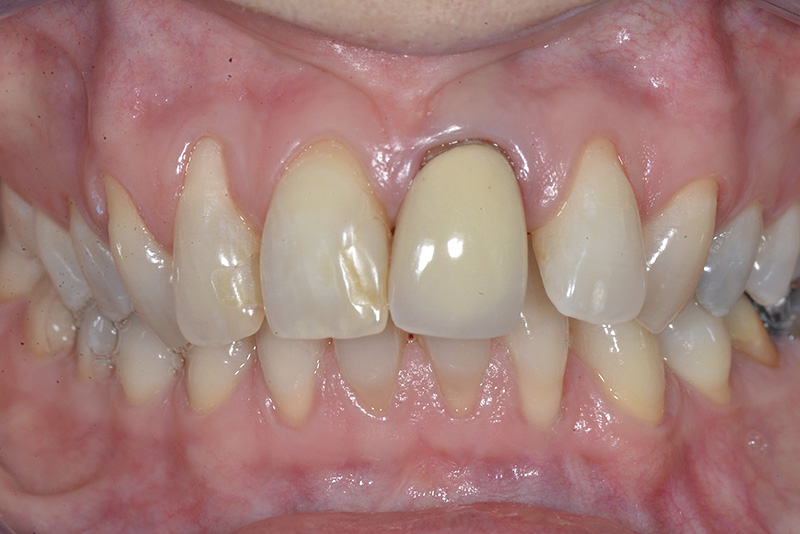

PREMESSA: in seguito all’estrazione dell’incisivo laterale superiore di destra, resasi necessaria per cause batteriche, si decide di affrontare il caso con il posizionamento di un impianto in sostituzione dell’elemento mancante dopo guarigione del sito infetto. Con tecniche rigenerative sia dei tessuti ossei mancanti a causa dell’infezione pregressa, sia dei tessuti gengivali che appaiono inizialmente troppo spostati in alto, si ripristina una corretta morfologia delle parabole (contorni) gengivali e delle papille interdentali (triangoli di gengiva tra due denti vicini).

Vengono utilizzati 2 tipi di provvisori: il primo, cementato ai denti vicini, viene utilizzato dal momento dell’estrazione del dente fino ad impianto osteointegrato (circa 6 mesi); il secondo, avvitato direttamente all’impianto, ha una funzione di prova estetica ma soprattutto di guida per la maturazione dei tessuti gengivali peri-implantari portandoli verso la maturazione completa prima di posizionare la corona finale in disilicato di litio.